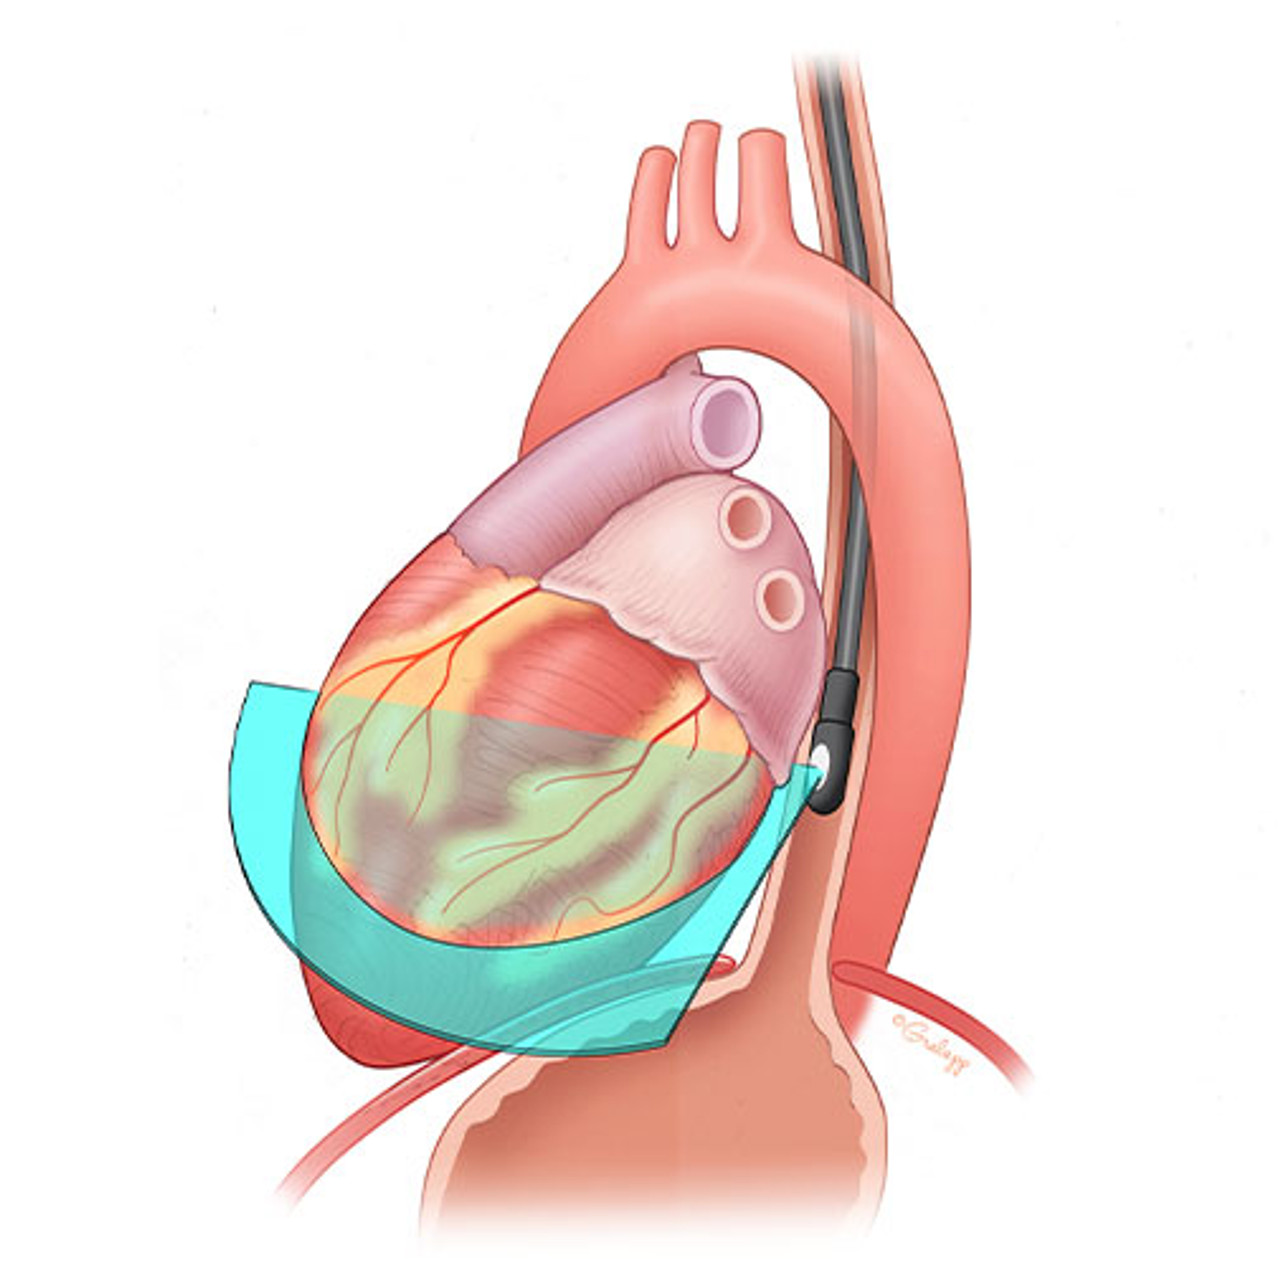

健康+医学 Transesophageal Echocardiography Transesophageal Echocardiography (TEE) | Heartplaceの詳細情報

Transesophageal Echocardiography (TEE) | Heartplace。PDF) Transesophageal Echocardiography in Clinical Practice。Transesophageal Echocardiography | Circulation。

Transoesophageal Echocardiogram - YouTube

題名:PracticalApproachtoTransesophagealEchocardiography,4thed.

著者:A.C.PerrinoJr.&S.T.Reeves(eds.)

出版社:WOLTERSKLUWER

ISBN:978-1-4963-8347-1

ページ数:643pp.

出版年:2020年

定価24,739円(本体22,490円+税)

題名:PracticalApproachtoTransesophagealEchocardiography,4thed.

著者:A.C.PerrinoJr.&S.T.Reeves(eds.)

出版社:WOLTERSKLUWER

ISBN:978-1-4963-8347-1

ページ数:643pp.

出版年:2020年

定価24,739円(本体22,490円+税)